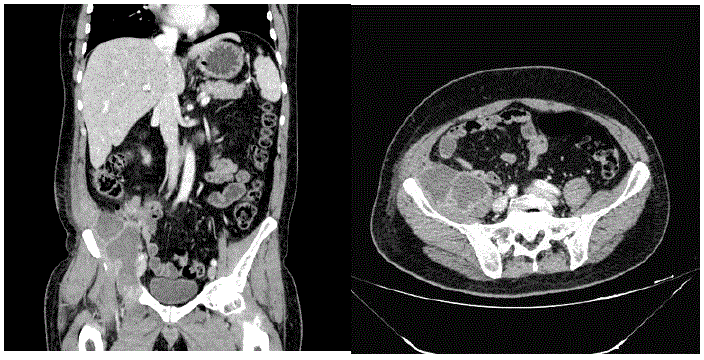

Realizada tomografia do abdome com os seguintes achados:

Qual é a melhor conduta no trauma abdominal?